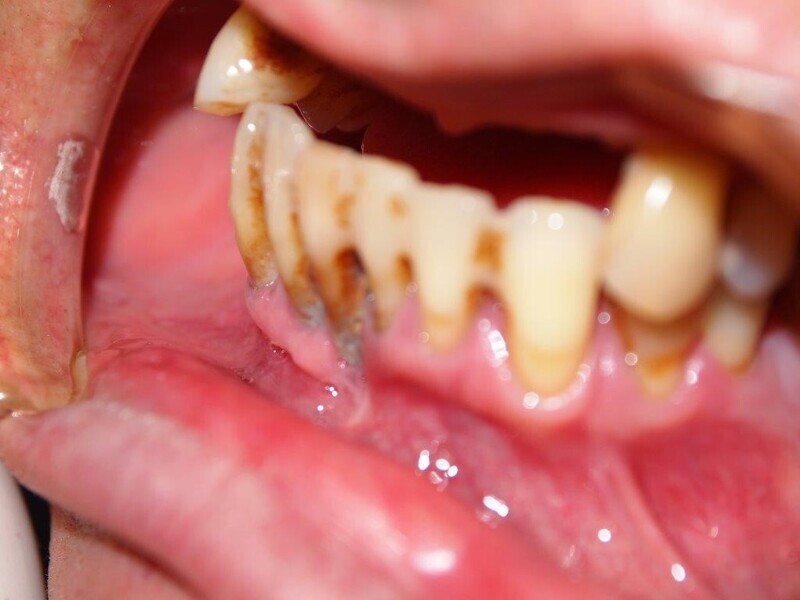

Implantacja z wykorzystaniem szablonu nawigacyjnego 3D